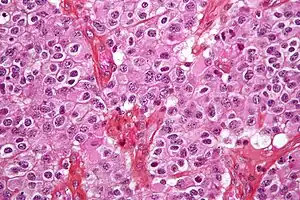

Oligodendrogliomas geralmente são tumores macios, cinzento ou rosados, que frequentemente comprimem parte do cérebro. Muitas vezes contêm depósitos minerais (calcificações), áreas de hemorragia e/ou cistos. Aparecem com mais frequência no lobo frontal, mediana frequência no parietal ou temporal e é incomum no occipital (razão de 3:2:2:1 respectivamente).[2]